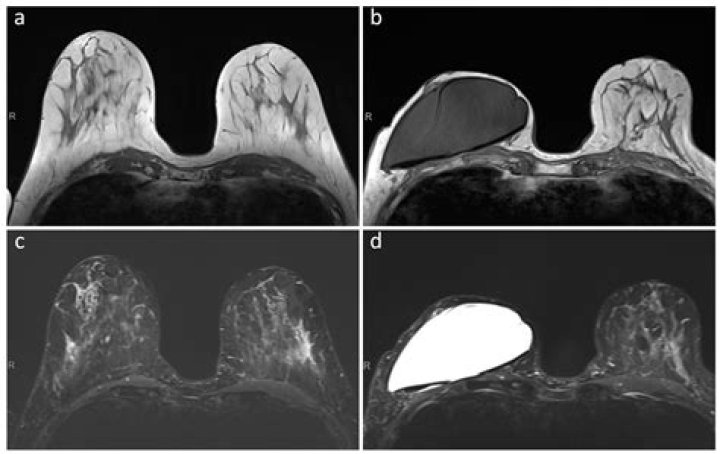

MRI is sensitive in detecting muscle inflammation, but it is not specific to a diagnosis of myositis because muscular dystrophies and other myopathies may have associated edema on MRI [2]. The signal changes on imaging need to be interpreted in the context of the clinical setting.

2. MRI scan. A scanner using a high-powered magnet and a computer creates images of the muscles. ...

When muscle is injured, the muscle swells up slightly, and holds on to water- this pattern of muscle swelling can be seen with an MRI. When that pattern is evident, that is another sign that myositis may be present.